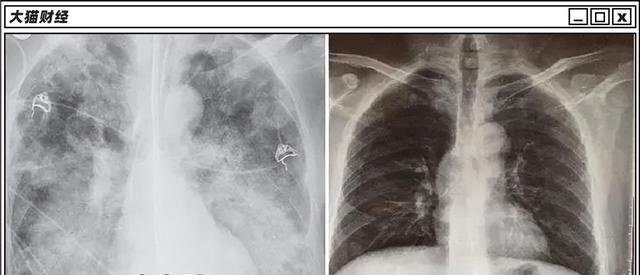

啥是白肺呢?

“白肺”全称为急性呼吸窘迫综合征(ARDS),一般指的是重症肺炎患者在X光或CT检查下,肺部显影呈一大片白色状而得名。

“沉默性缺氧”侵蚀老年人,“白肺”已经开始侵蚀青少年,均与呼吸相关,于是,新的财富密码又出现了,血氧仪和制氧机开始大卖。